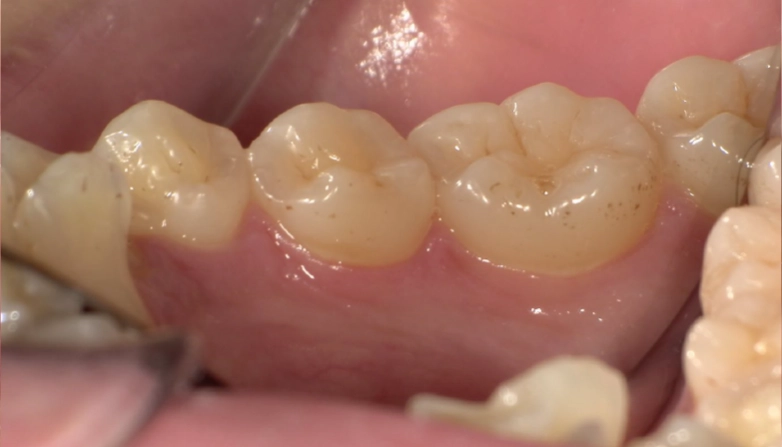

症例1

before

after

| 主 訴 | 着色が気になる |

| 治療期間 | 通院 1回 |

| 治 療 費 | 1回 7,700〜11,000円(税込) |

| 治療内容 | PMTC |

| 治療のリスク | 歯自体の色を白くすることはできない。 歯と歯の間や強い着色などは落とすことが出来ないことがある。 しばらくすると再び着色することがある。 |